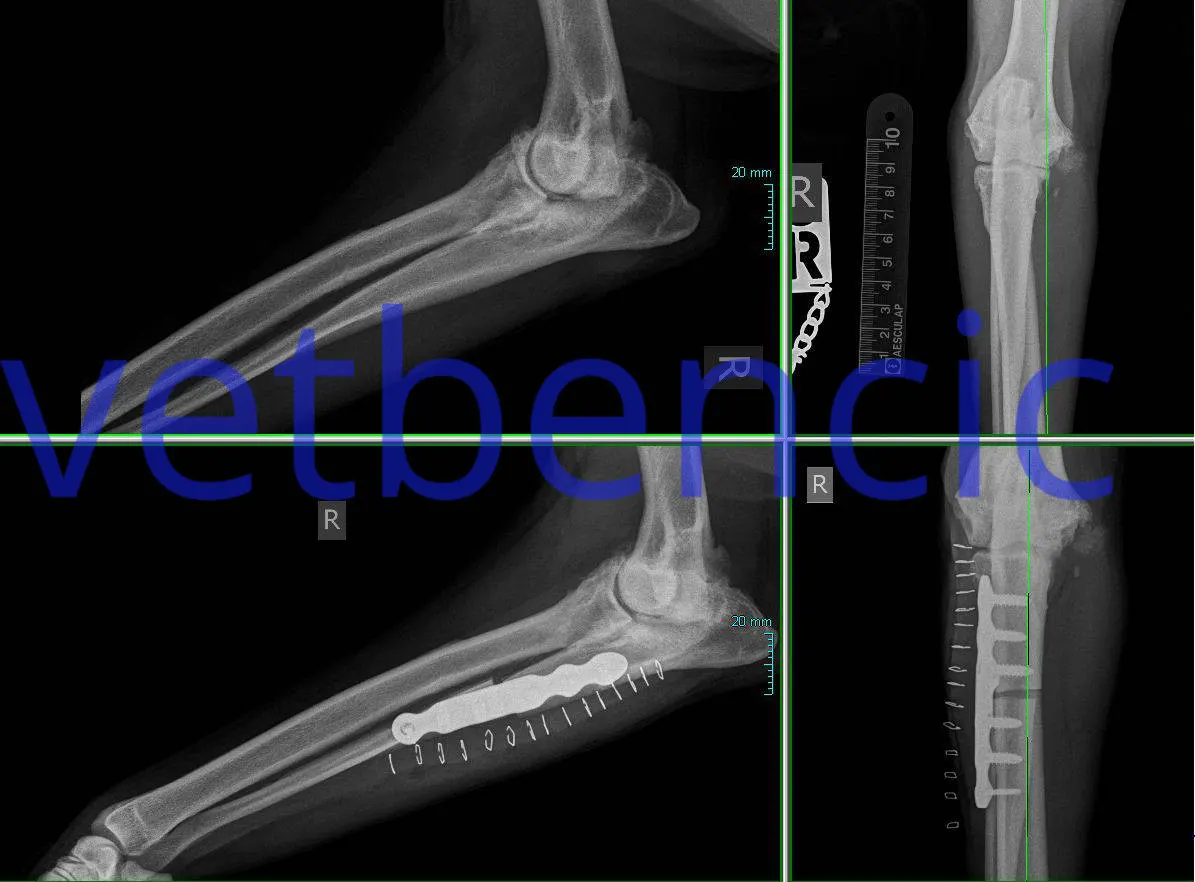

Ove tehnike mijenjaju geometriju koljena na takav način da ligamenti više nisu potrebni za održavanje stabilnosti koljena. Postoji nekoliko tehnika koje uključuju promjenu oblika vrha tibije tako što se napravi rez na kosti i na taj način se postavi u novi položaj:

Ova operacija uključuje pravljenje polukružnog reza na vrhu tibije i rotiranje platoa tibije dok prethodni nagib kosti više ne nestane. Kost se naknadno fiksira odgovarajućom pločicom i vijcima.

Ova operacija uključuje iste principe kao i TPLO, s rezom na tibiji kako bi se omogućila promjena geometrije. Osnovno načelo je da promijenjeni smjer istezanja skupine mišića kvadricepsa proizvodi sile preko zgloba koljena koje neutraliziraju tendenciju bedrene kosti da klizi niz kosinu tibijalnog platoa. I TTA i TPLO imaju za cilj napraviti kut između tibijalnog platoa i patelarne tetive pod pravim kutom, čime se suprotstavlja tendenciji bedrene kosti da klizi niz kosinu tibijalnog platoa. Budući da kost zacjeljuje učinkovitije od ligamenata, ove metode pružaju mnogo veću čvrstoću od metoda popravka ligamenata. Oporavak je puno bolji, psi već 1-3 dana nakon operacije hodaju na bolesnoj nozi. Brz povratak normalnim aktivnostima vrlo je važan za teške pse, atletske pse, pse s blagom hromošću i za pacijente koji imaju bilateralne rupture. Kod takvih se TPLO može izvesti na oba koljena istovremeno. Koja je metoda prikladnija ovisi o individualnim anatomskim karakteristikama životinje. U većini slučajeva obje su metode primjerene.

Preporuča se napraviti artroskopiju kako bi se pregledale ostale strukture u zglobu.

U slučajevima kada je meniskus oštećen, radi se meniskotomija, odnosno odstranjivanje dijela meniskusa. Oporavak meniskusa događa se u posebnim okolnostima.

90% pasa liječenih TTA ili TPLO vraća se normalnim aktivnostima.

To znači da vlasnici više ne primjećuju nikakve znakove šepanja kod kuće.

Radni psi nakon ovih intervencija mogu se vratiti u službu. Pravilnim odabirom operatera prilikom planiranja operacije obje tehnike imaju visok postotak uspješnosti.

Komplikacije su manje nego kada se radi intervencija bočnim šavom.

Dvije najčešće komplikacije su infekcija i mehaničke komplikacije.

Infekcija se liječi antibioticima. U najgorem slučaju, bakterija je na implantatu i tada se implantat mora izvaditi kada kost zaraste. Kod većine pacijenata implantat ostaje doživotno, ne mora se vaditi. Mehaničke komplikacije nastaju kod previše aktivnih pasa u razdoblju dok kost ne zaraste (6 tjedana). Takve se komplikacije obično rješavaju mirovanjem, a ponekad se mora učiniti i revizija.